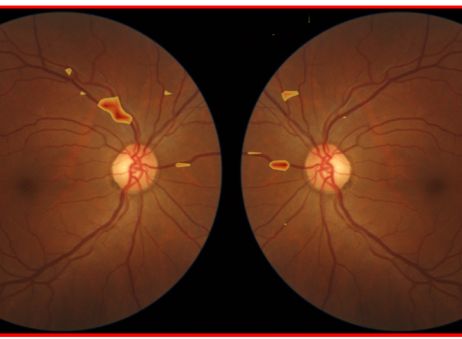

El proyecto español ‘Aitheroscope’, desarrollado por Horus ML, ha sido seleccionado como uno de los cuatro finalistas de la novena edición de los ‘Premios a la Innovación Social’ impulsados por la Fundación Mapfre, en colaboración con IE University como socio académico.